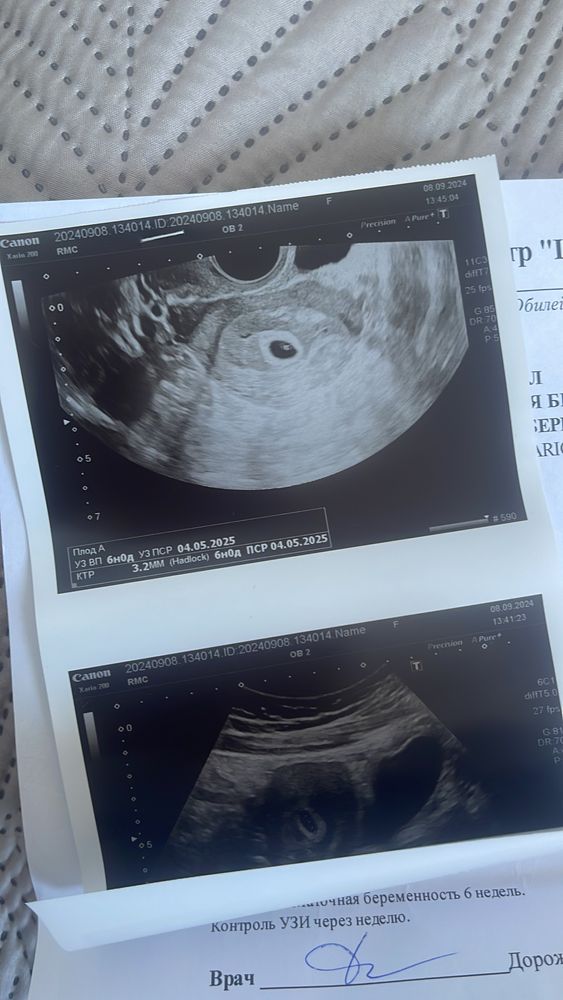

Девочки! скажите пожалуйста, кто сталкивался с такой ситуацией? срок беременности ровно 6 недель сердцебиение пока не услышали, но малыш развивается по своему сроку, сказали ,если через неделю придёте и опять сердцебиение не будет, то это замершая беременность очень сильно переживаю. Все ли совпадает по размерам?

интересные такие, пишут желточный мешочек не визуализируется, а внизу размеры)))

А чего у вас два заключения в одном протоколе,она что ли не удалила и просто дописала,первое там вообще ранний срок пя 3,5 мм без жм,а второе уже пя 12 мм,жм 2,7 и ктр 3,2 без сб,я так понимаю ваше второе,ну да надо подождать,может у нее аппарат не очень,у большинства с ктр 3 уже если не сб,то пульсация есть и ее видно

Заключение кошмар. То одно пишут то другое. Так не делают. Если у вас по факту то что внизу то все в пределах нормы. На фото вроде видно эмбрион. Теперь через недельку сходить повторно услышать сердечко